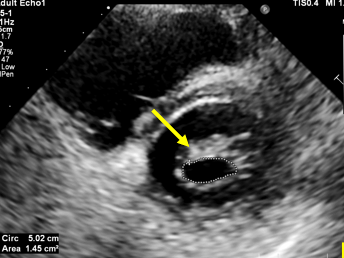

2、单选题:

请问图中显示的瓣膜呈“鱼嘴样”开放指的是哪一种疾病:( )

选项:

A:二尖瓣狭窄

B:主动脉瓣关闭不全

C:二尖瓣关闭不全

D:主动脉瓣狭窄

答案: 【二尖瓣狭窄】